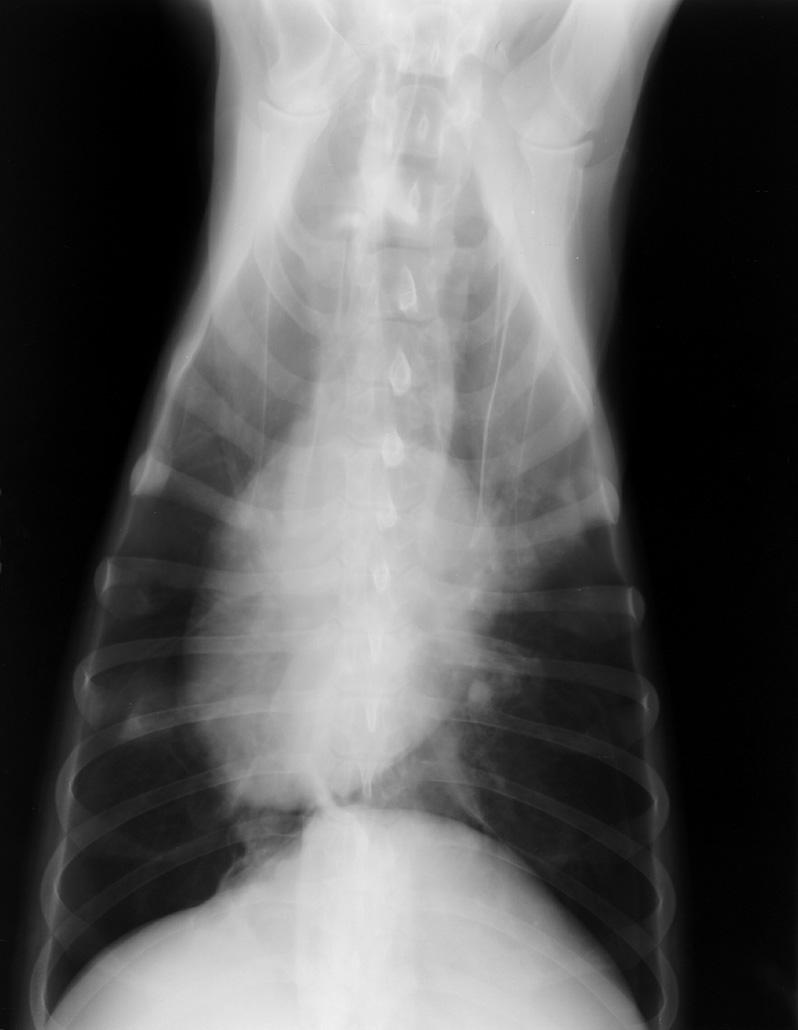

Oils on your hands can affect the x-ray emulsion and casue these artifacts. Handle only be the edges.